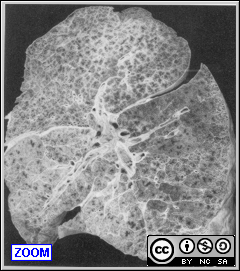

Two clinical entities: acute and chronic form: